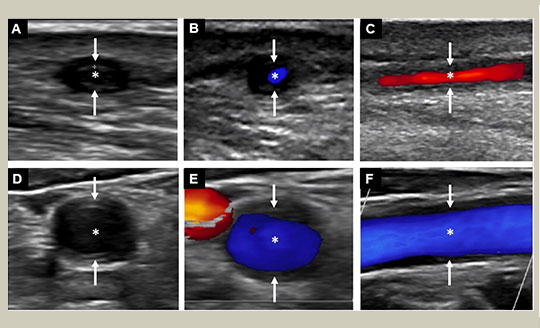

Nephrologie

Zystennieren

Priv.-Doz. Dr. Michael Rudnicki, FASN 30.5.2022

Einfache Nierenzysten treten mit zunehmendem Lebensalter auch bei gesunden Personen gehäuft auf. Nierenzysten finden sich bei vielen seltenen (angeborenen und hereditären) Nierenerkrankungen. Die ADPKD (autosomal dominante polyzystische Nierenerkrankung) ist die häufigste seltene Zystennierenerkrankung mit Tolvaptan als aktuell einzige zugelassene spezifische progressionshemmende Therapie.